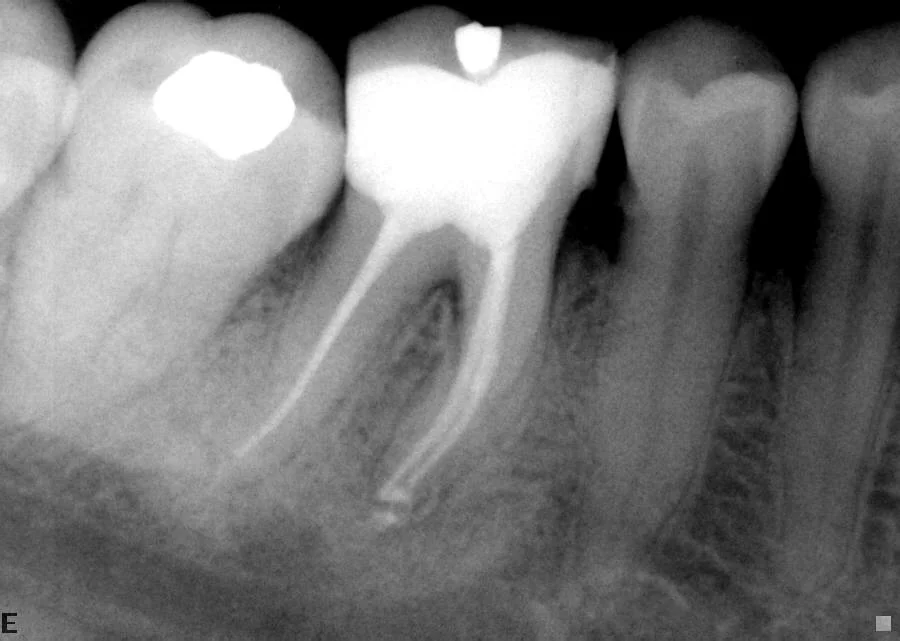

After: Infected lower left teeth